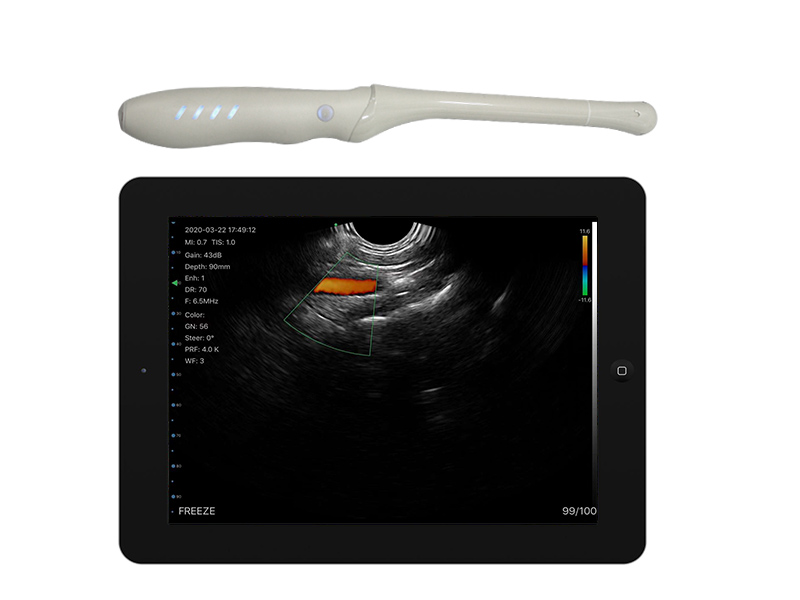

5T transvaginal palm doppler ultrasound scanner

5LT 2in1 palm doppler ultrasound scanner

4T transvaginal palm doppler ultrasound scanner